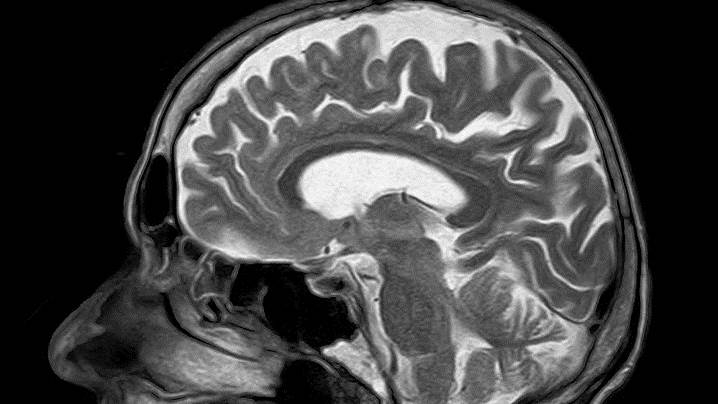

Mozak "punoljetan" tek sa 30 godina

Ljudski mozak postaje "punoljetan" tek sa 30 godina, odnosno sazrijeva sporije, navode naučnici sa univerziteta Oxford i Cambridge.

Prelazak mozga iz djetinjstva u odraslo doba odvija se tokom tri decenije, pa mozak do tridesete godine nije u potpunosti razvijen.